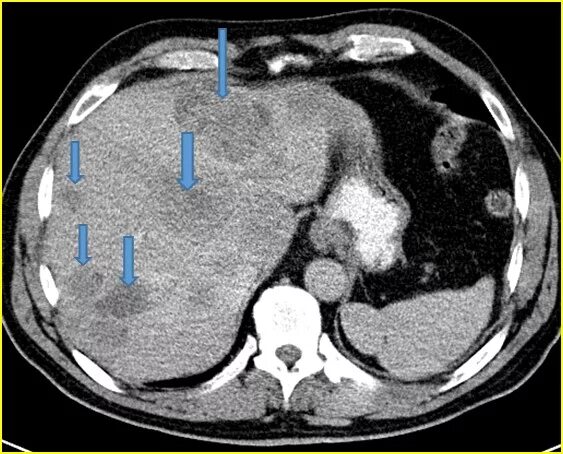

Цирроз на кт